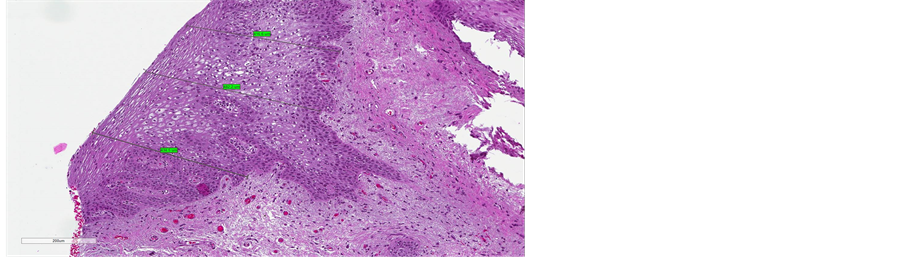

Before treatment, the stratified squamous epithelium appeared atrophic and thin, with no evidence of the crests of the Malpighian layer and epithelial papillae, and with a flattened sub-epithelial junction (Figure 4(a), Figure 5(a), Figure 6(a)). Post-treatment histology samples showed restoration of the epithelial and subepithelial structures, characteristic of reproductive-age vaginal mucosa

(Figure 4(b), Figure 5(b), Figure 6(b)). Immunostaining for collagen III and IV demonstrated a visible post-treatment enhancement. Microscopic examination of the biopsy sections revealed a striking increase in the thickness of epitelium, with resurfacing of the Malpighian layer and epithelial papillae. The median improvement from baseline in epithelium thickness was 97% (range: 9% - 203%).

Figure 4. (a) pre-treatment section of epithelium (maximum measure of 300 µm); (b) post-treatment section of epithelium (maximum measure of 1133 µm).

evaporation of water from within the target cells. The fractionated/pixel CO2 laser treatment used in this study triggers superficial thermo-ablation, and deep thermal cell activation to stimulate tissue remodelling. The process involves a small family of proteins, known as heat shock proteins (HSP), which is activated, [18] [19] leading to a change in cell metabolism and selective induction of ex- pression of certain receptors on the surface of the cells of the treated tissue [20] [21] . Among these, sub-types 43, 47 and 70 are overexpressed, and act as chaperones to collagen, and also play a predominant role in the induction of growth factors, such as TGF-β, a key cytokine in the inflammatory and fibrogenetic processes that produce collagen and extracellular matrix [22] [23] . This cascade of events stimulates restoration of metabolic trophism of the vaginal mucosa, which improves its elasticity and moisture, and provides relief from discomfort in menopausal women. The present findings demonstrated that fractional/pixel CO2 laser treatment stimulated tissue remodelling, neocollageno genesis and reconstruction of the trabecular architecture typical of collagen. The thickened epithelial papillae, with enhanced production of glycogen, contributed to improved moisture and objective characteristics of the vaginal mucosa, as expressed in improved VHI-S and histologically evident qualitative and quantitative changes